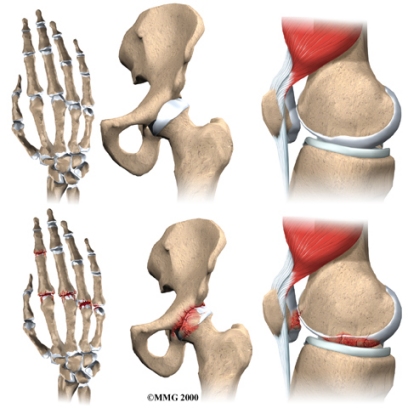

Where does OA develop?

OA is most common in the small joints of the hands, the spine, the knees, the hips, and certain toe joints. OA primarily affects the articular cartilage, the slippery, cushioned surface that covers the ends of the bones in most joints and lets the bones slide without rubbing. Articular cartilage also functions as a shock absorber.

In OA, the articular cartilage becomes damaged or worn away. As this happens, the joint no longer fits together well or moves smoothly. In the early stages of OA, the cartilage actually becomes thicker as your body tries to repair the damage. The repaired areas are more brittle than the original cartilage, and these brittle areas begin to wear away and become thin. They may even wear away entirely. This eventually leads to a condition called eburnation, in which the bones become thick and polished as they rub together. X-rays can show these changes in the cartilage and bones.

But OA is not just a disease of the cartilage. The damage to the cartilage seems to start a sort of chain reaction that involves all the parts of the joint. Bone spurs, or outgrowths, often begin to form around the edges of the joint. The joint capsule (the watertight sack around the joint) can become thickened and lose its stretch. The synovial membrane that lines the inside of the joint capsule may become inflamed (swollen, red, hot, and painful), and crystals may form in the synovial fluid. The tendons and ligaments around the joint can also become inflamed.